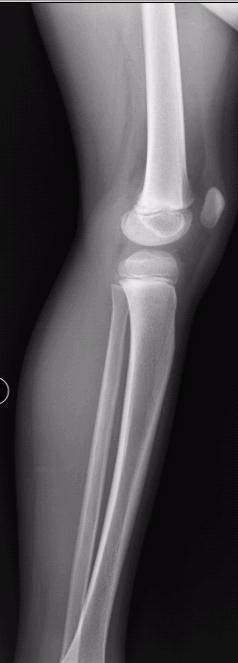

左胫骨中段前缘局限性骨皮质增厚,其内隐约见一低密度影,考虑骨样骨瘤可能,局限性骨皮质增厚可能,建议ct进一步检查。最后一张片子应该是l吧。

左胫骨前缘骨皮质增厚,有向前凸起改变,与之比较右侧胫骨皮质均匀光整。支持二楼的意见。从骨性标记看,小腿的左右标注楼主有误。

左胫骨中段前缘局限性骨皮质增厚。